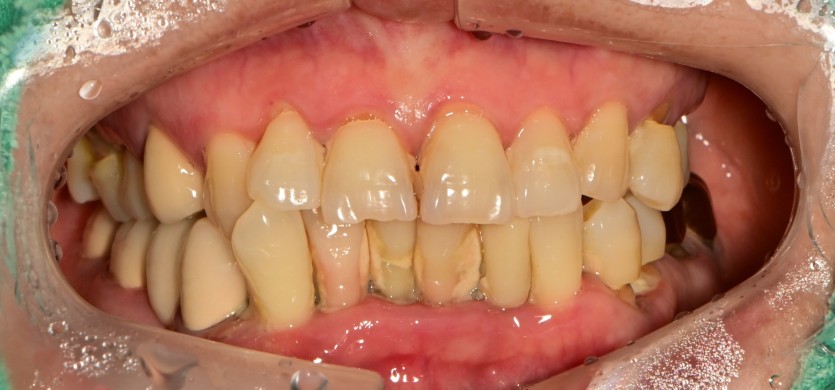

만 61세 전체 임플란트 증례

전체 임플란트 증례입니다.

18개의 임플란트로 완성하였습니다.